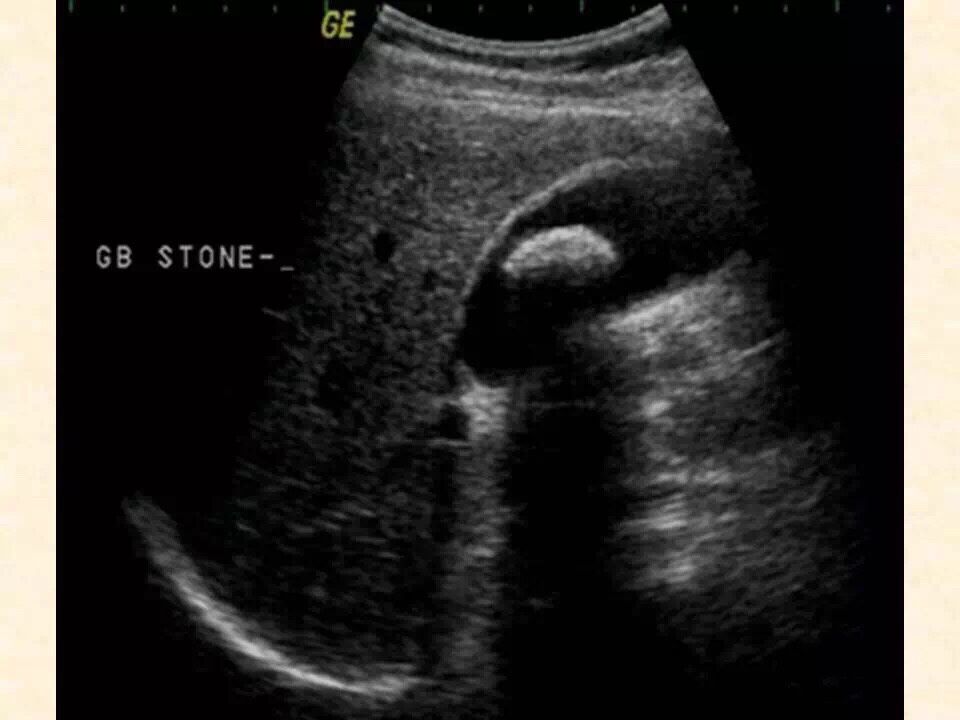

1、消化系统:肝胆胰脾的超声检查。

| 陆丹斌 锡山区鹅湖人民医院功能诊断科副主任,主治医师,2011年毕业于徐州医学院,进入鹅湖人民医院诊断科工作十余年,具有丰富的超声和心电图检查诊断经验。擅长各类腹部占位、结石,甲状腺和乳腺良恶性结节,妇科子宫肌瘤、宫外孕、盆腔炎症,产科、儿科、心脏和血管等常规和疑难病例诊断;同时擅长心电图、动态心电图等的常规和疑难病例检查。多次获得院内外先进表彰,在核心期刊发表论文数篇。 |